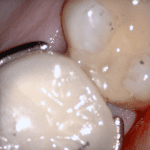

This case was scanned by two different scanners. Once by the Medit i500 and another time with the Aoralscan. Both the meshes are included so you can compare the two. It was scanned to deliver a case that retrofits a partial denture